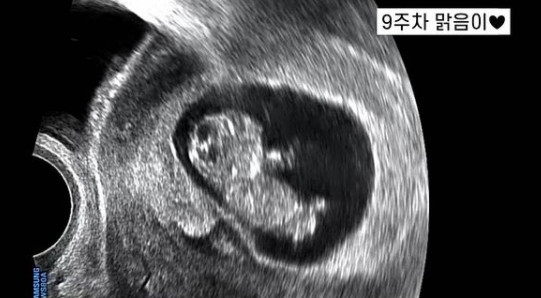

그는 "너무 빨리 생긴 거라 당황하기도 했지만 깜짝 선물이라 더 소중하다. 뱃속 아가 이름은 '영혼이 맑은 아이'로 자라라는 뜻으로 맑음이라고 지었다"라며 "맑음이는 임신 23주차 아가가 됐다"라고 밝혔다.

뱃속 아가의 이름은 '영혼이 맑은아이' 로 자라라는 뜻의 '맑음이' 라고 지었어요.